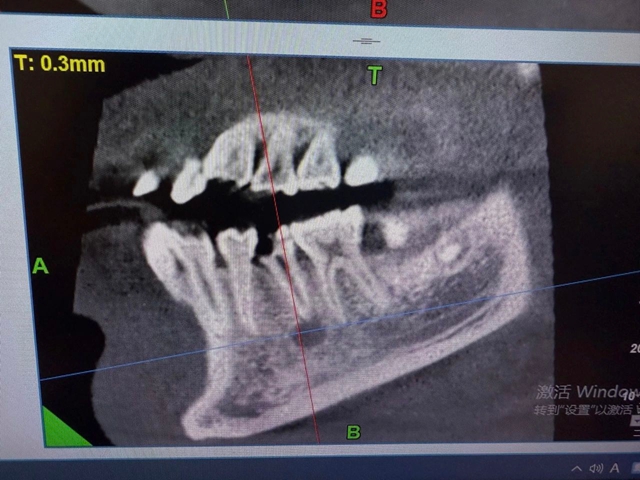

影像学检查进一步揭开真相:根尖X线片发现45牙根尖有5mm×7mm的暗影;CBCT清晰显示颊侧骨板已被破坏,感染顺着咬肌前间隙扩散,形成了的脓腔,最终突破皮肤形成面部瘘口。血常规检查中白细胞、中性粒细胞和CRP等感染指标均显著升高,证实了严重的细菌感染状态。

术前影像学资料